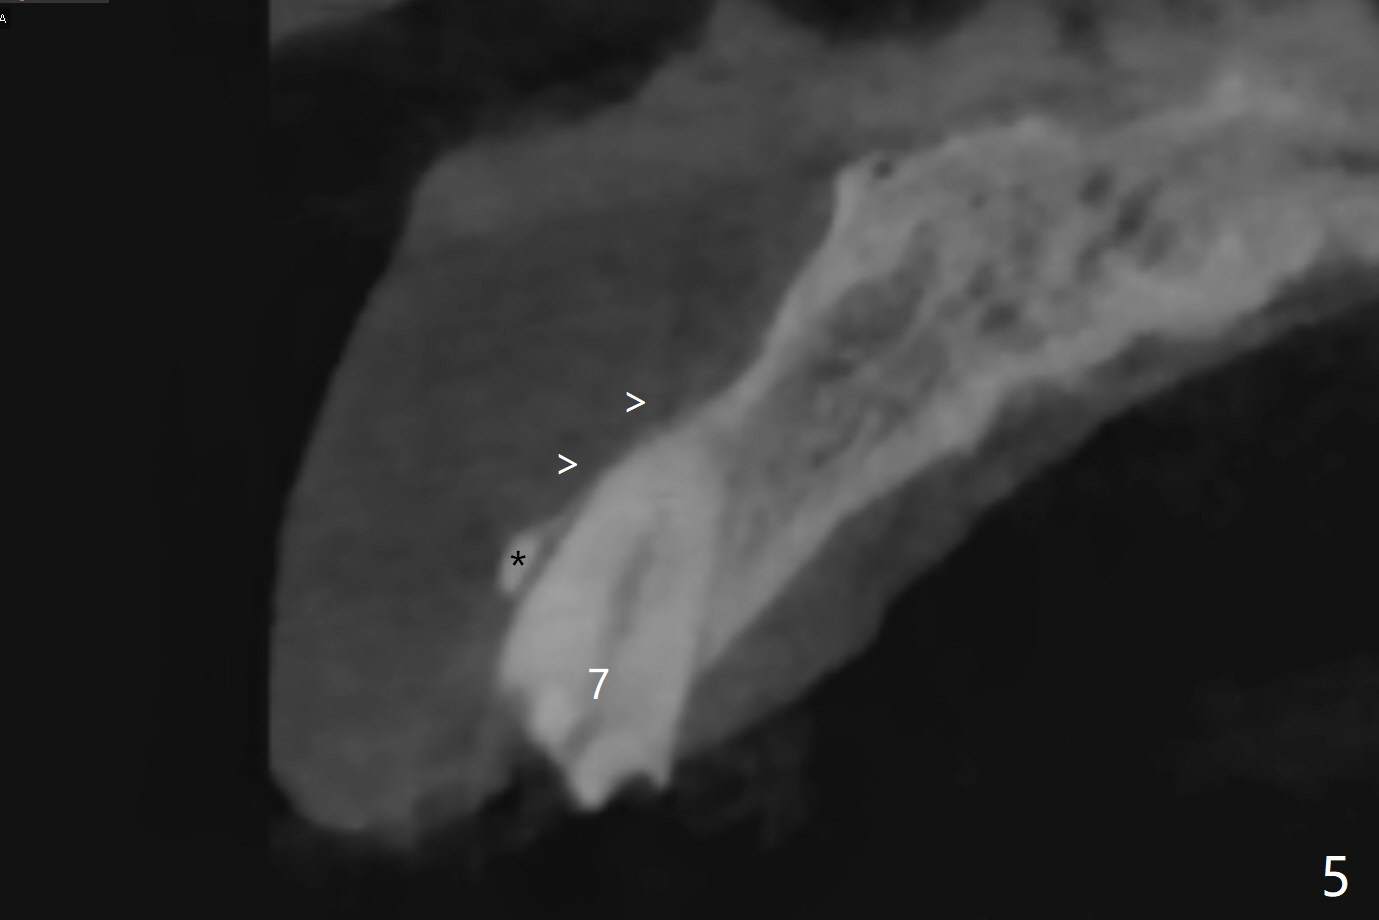

A 79-year-old man, who fractured the tooth #7, has several Class V defects (Fig.1). He seems to be a bruxer. Pay attention to occlusion and determine whether he has anterior deep bite. The neighboring tooth, #6, has apical lesion (Fig.2 <). Root canal therapy has been finished prior to implant placement (Fig.3). Prepare Tatum 1-piece implant in case the trajectory is off. If the crown height is more than 10 mm, prepare IS system. Otherwise use DIO one. If the root turns out to be difficult to extract, be ready for socket shield. Preop CT shows minimal apical perforation at #7 (Fig.4 (3-D image)). The buccal plate is thin (Fig.5 (coronal section) between arrowheads (acute infection may increase the perforation quickly)), while the crest is thick (*).